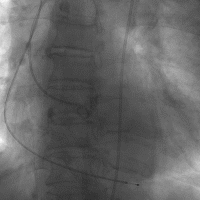

TTE确认AS严重性

● LVEF: 30%

● LA 5.47 cm LVEDd 6.05 cm

● Severe aortic stenosis

▷ AVA: 0.52 cm2

▷ Vmax: 4.3 m/s

▷ Mean gradient: 42 mm Hg

● Mild AR

● Severe MR

● Severe TR

Figure 1

TTE评估

来自浙江大学医学院附属第二医院的余蕾医师分享了超声方面的临床经验,心脏超声评估主要包括三个方面的内容,首先,对心脏瓣膜整体形态结构等进行测量,对主动脉瓣形态结构进行评价,判断是否为二叶式主动脉瓣畸形、测量瓣叶厚度、钙化部分是否均匀等。

其次,测量有效瓣口面积、最大跨瓣流速、平均跨瓣压差等进行评估瓣膜狭窄程度,通过放大模式清晰显示主动脉瓣结构,再通过血流动力学观察、判断主动脉瓣反流程度。

最后,对心脏整体功能进行评价,判断心功能,观察二尖瓣和三尖瓣的血流动力学,判断是否存在狭窄、反流,以及狭窄和反流的程度。另外,需评价心脏是否存在心包积液、肺动脉高压。